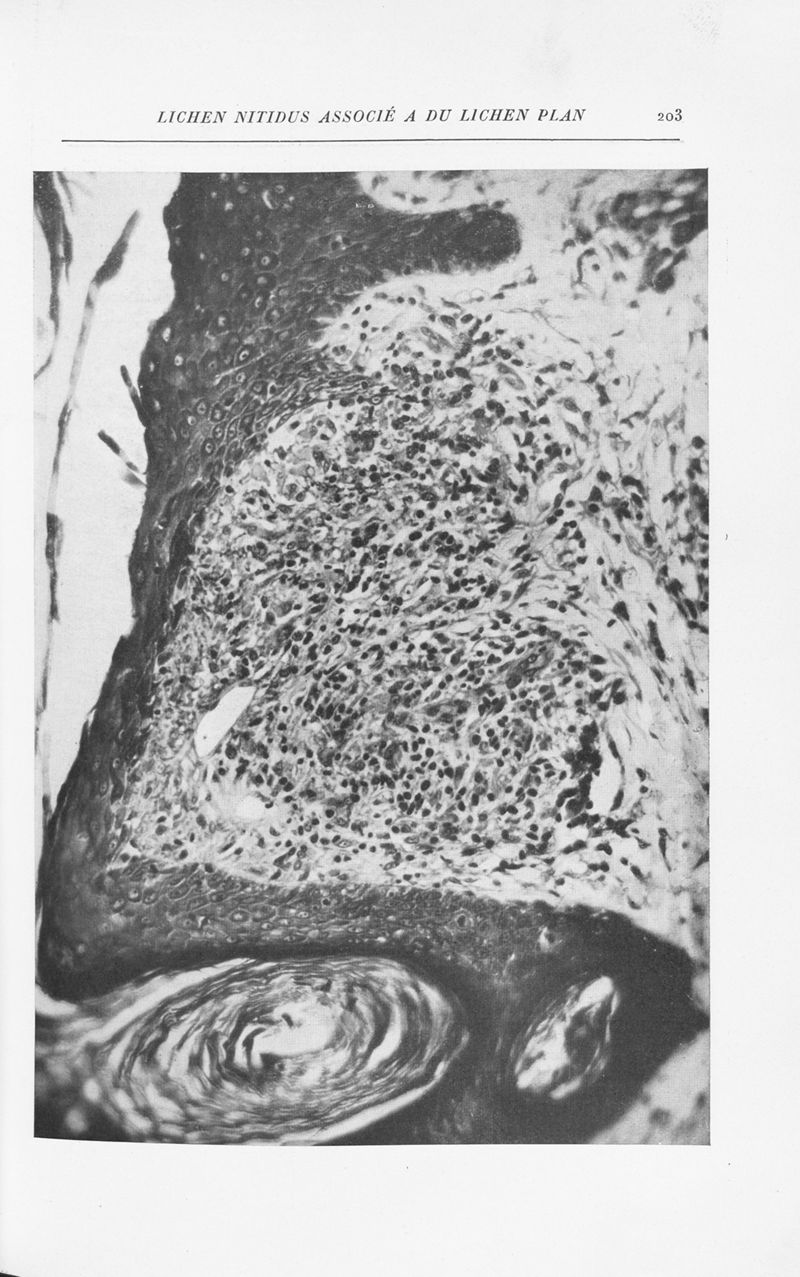

Annales de dermatologie et de syphiligraphie

7ème série, tome VIII. - Paris : Masson, 1937.